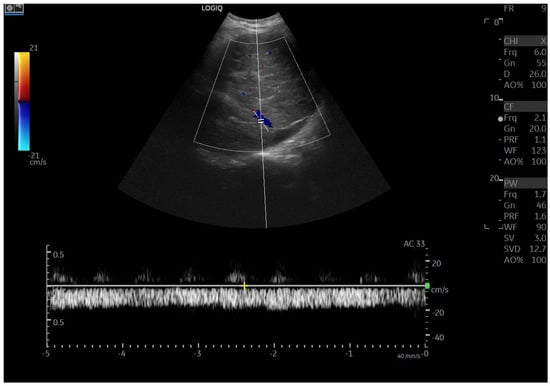

Doppler patterns in Fontan patients resemble those observed in chronic liver disease, including reduced portal flow velocity (mean flow velocity < 14 cm/s) [56]. The Fontan procedure inevitably alters hepatic venous waveforms on Doppler US (Figure 10, Figure 11, Figure 12 and Figure 13). Inverted portal flow has a specificity of 100% for diagnosing PHTN [57] (Figure 12). The hepatopetal phase pattern in the hepatic vein differs between patients with total cavo-pulmonary anastomosis (including both lateral tunnels and extracardiac conduits) and those with atrio–pulmonary connection [58,59,60]. In atrio–pulmonary connection, hepatopetal flow is preserved (Figure 10), reflecting the exclusion of atrial contribution to venous circulation, whereas in total cavo-pulmonary anastomosis, flow reversal (Figure 11) occurs only during early expiration. Similarly to congestive heart failure, hepatic veins and the IVC are dilated, with abnormally increased hepatic vein pulsatility, regardless of the anastomosis technique [54,61,62]. The loss of the normal three-phase Doppler pattern in hepatic veins is universal following bi-cavo-pulmonary surgery due to the absence of atrial contraction. The presence of a monophasic pattern indicates advanced liver injury [63].

Figure 10.

Doppler Ultrasound of the middle hepatic vein showing the loss of the normal three-phase pattern due to the absence of atrial contraction.

Among individuals with Fontan physiology, the hepatic veins typically show a dampened, predominantly hepatopetal monophasic waveform, reflecting the presence of long-standing hepatic congestion. Venous flow velocities are markedly reduced compared with those measured in healthy individuals [63,64]. In contrast, in later stages characterized by cirrhosis and increased hepatic stiffness, further dampening or paradoxical changes in the venous flow pattern may be observed [37,56,64].

In particular, the hepatic venous Doppler waveform offers valuable insight into hemodynamic changes over time. In the early post-Fontan period, in the absence of atrial contraction and before structural liver damage is evident, the hepatic venous flow may display a relatively blunted monophasic or biphasic waveform with reduced phasicity, reflecting the lack of pulsatility and elevated central venous pressure [37,56,64].

As FALD progresses, and especially in the setting of developing cirrhosis, the Doppler waveform may become more dampened or even flat, corresponding to the increasing stiffness of the hepatic parenchyma, reduced compliance of the vascular bed, and worsening portal hypertension [37,56,64]. Simultaneously, the hepatic veins may appear dilated in the early and mid-stages of disease due to chronic venous congestion, but may show reduced caliber in later stages as fibrosis progresses and vascular remodeling occurs [37,56,64].